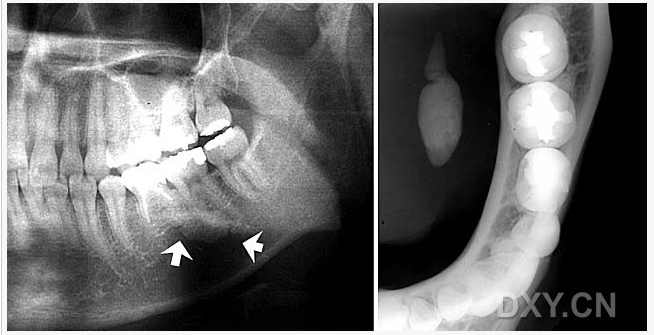

頜骨骨折

牙源性鈣化囊腫

牙瘤!

牙源性鈣化囊腫    牙瘤!

牙瘤